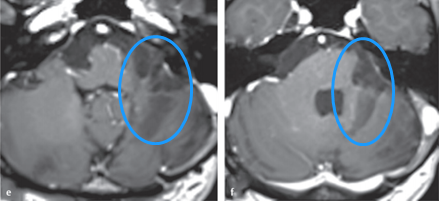

Stupp方案:在放療期間口服TMZ75mg/(m2 ·d),連服 42d;間隔 4 周,進(jìn)入 輔助化療階段,口服TMZ 150~200mg/(m2 ·d),連用 5d,每 28d 重 復(fù),共用 6個(gè)周期。術(shù)后4年,患者可以完全獨(dú)自生活,延髓(圖e)和腦橋(圖f)軸位t1加權(quán)磁共振增強(qiáng)掃描未見腫瘤殘留或復(fù)發(fā)。

H男士術(shù)后MR影像